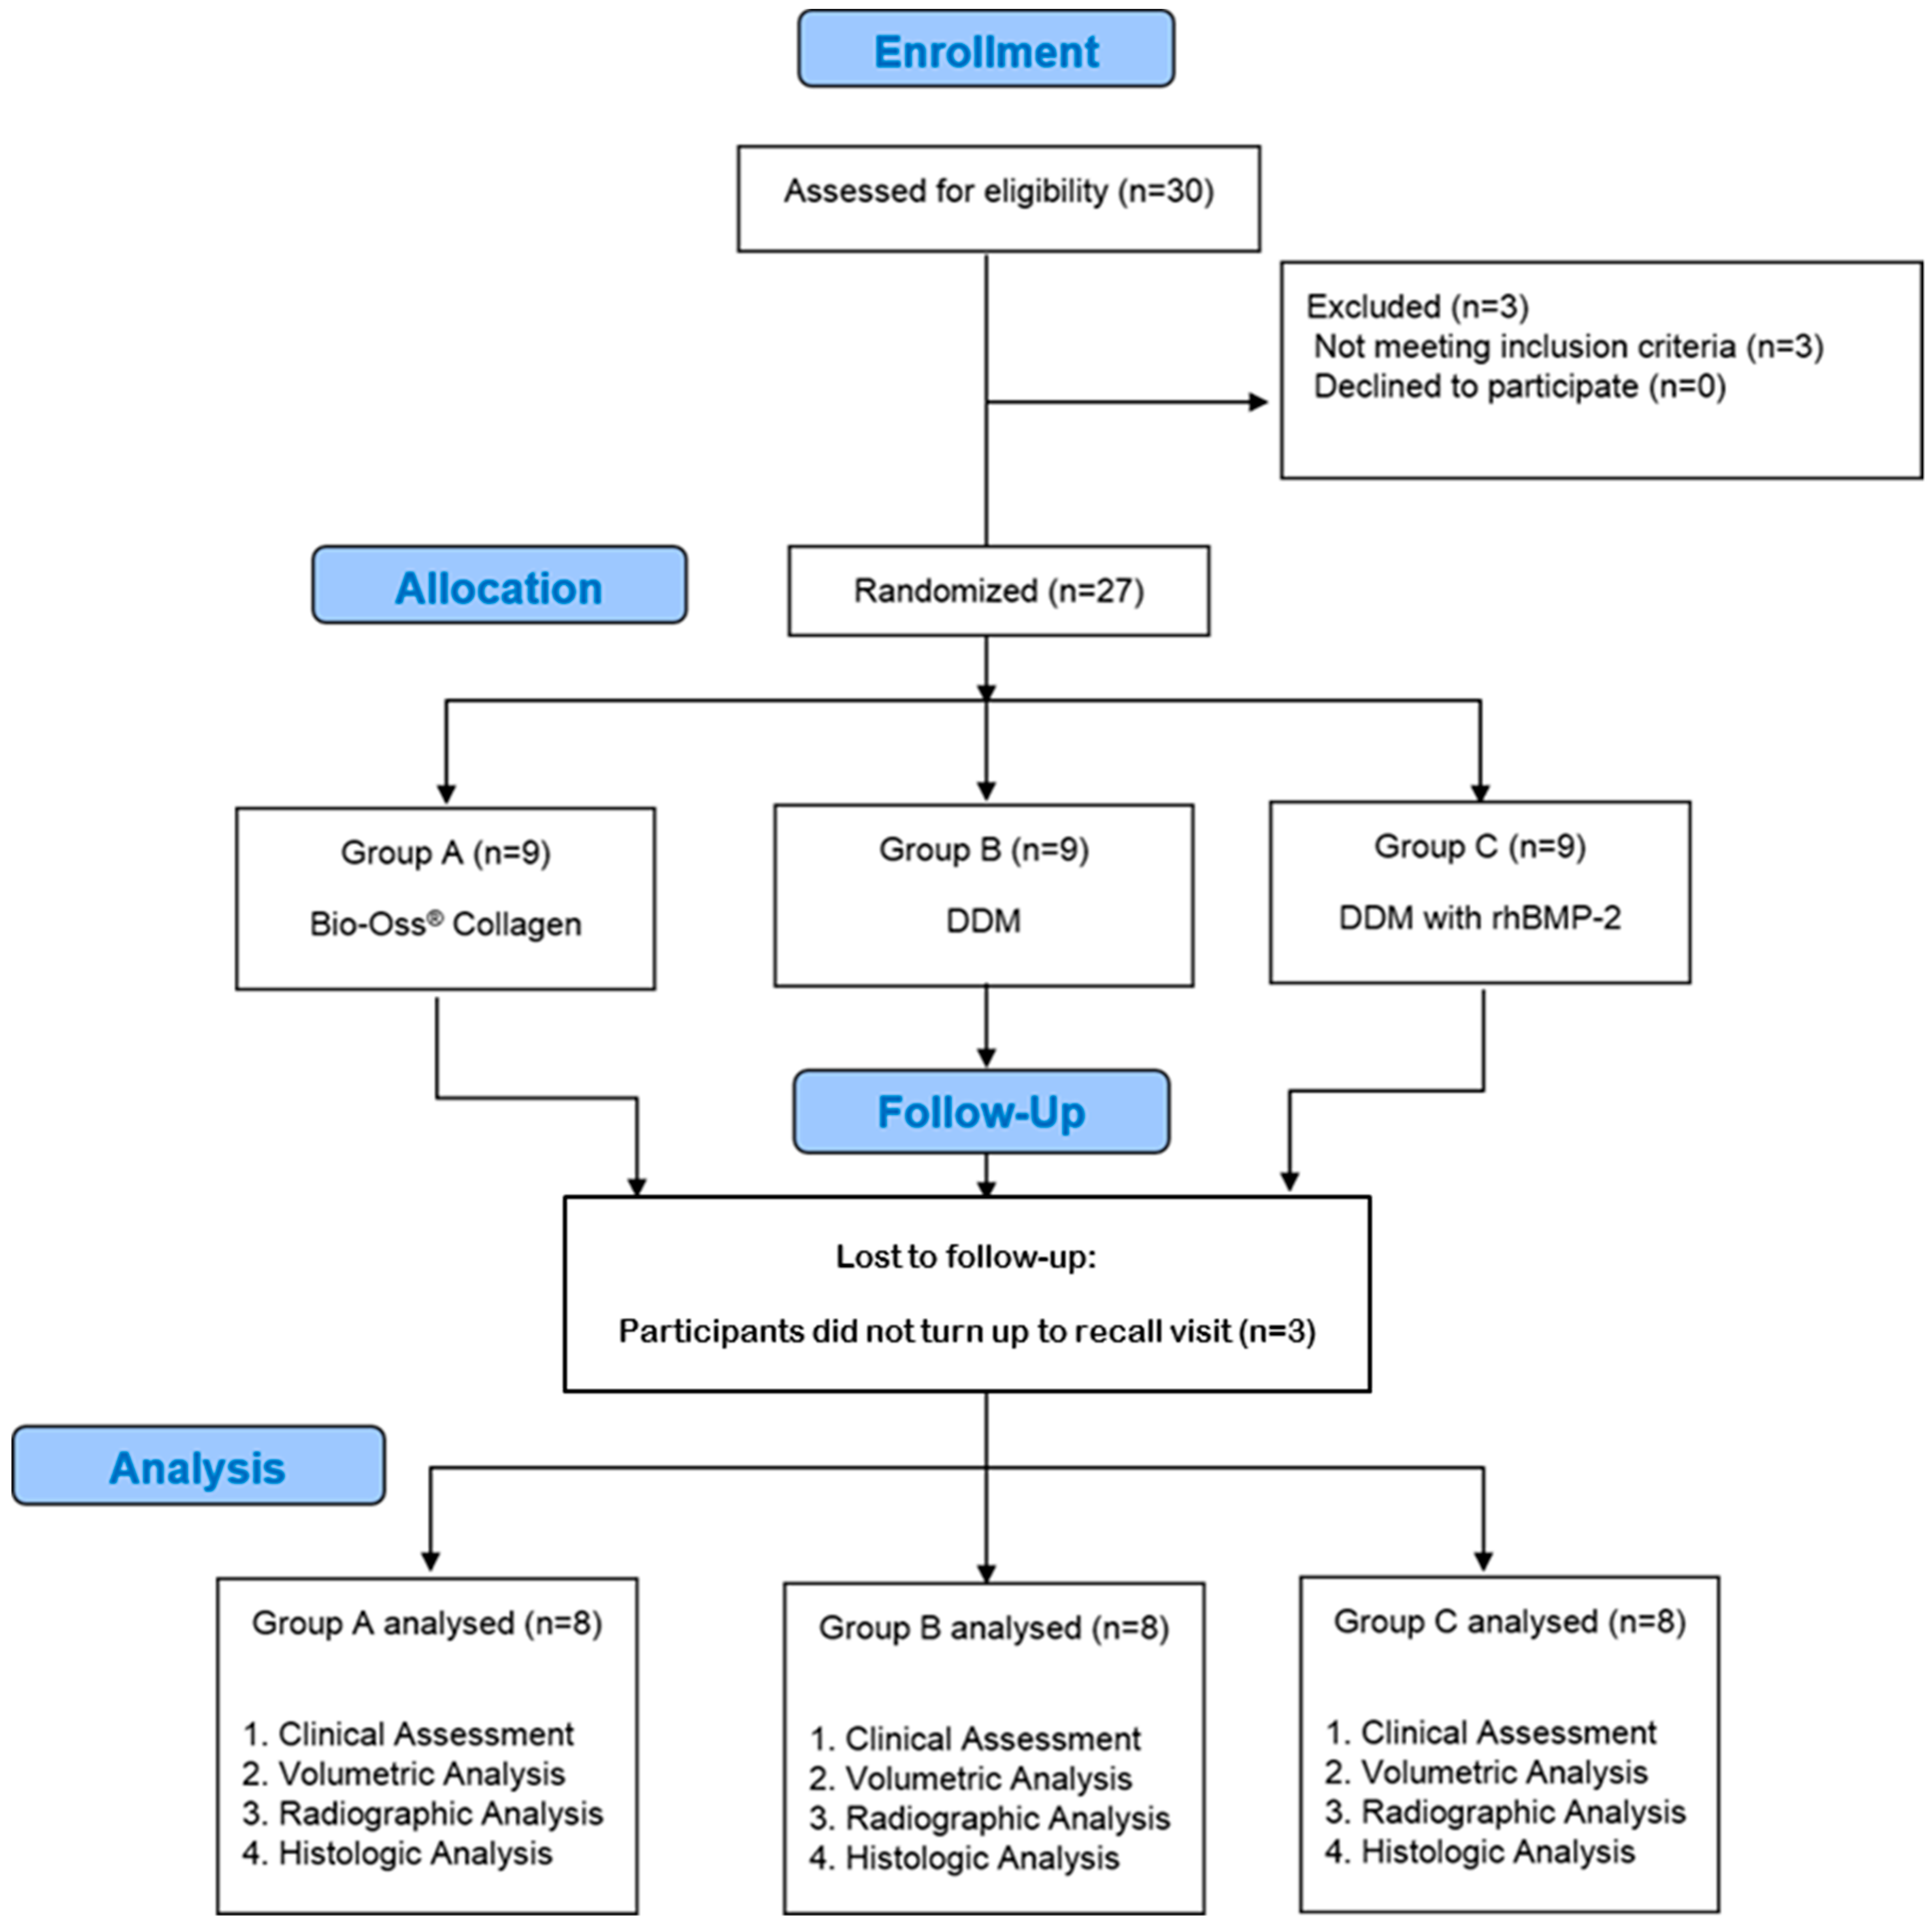

2. Materials and Methods

2.1. Enrollment of Patients

2.2. Randomization Procedure